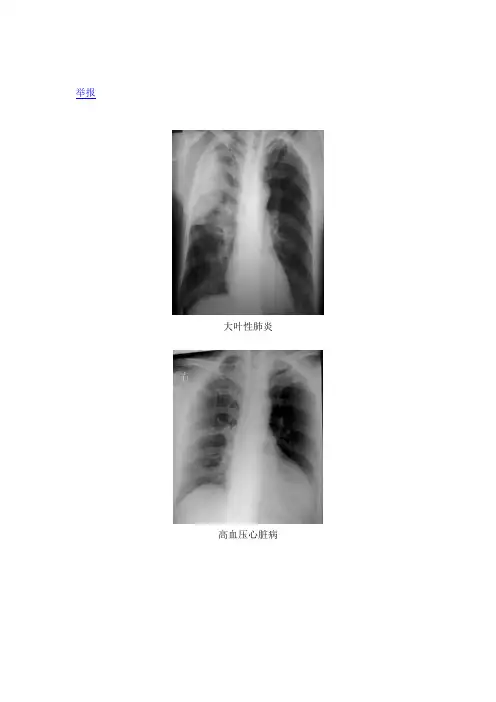

举报大叶性肺炎高血压心脏病消化道穿孔胸腔积液胸椎压缩性骨折右侧气胸右侧胸腔积液右肺炎右胫腓骨骨折右上肺炎右中叶肺炎正常胸片左侧胸腔积液左肱骨骨折风心病,梨型心胸部X线片系统读片原理24个字母(A-X)系统读片法,可以减少漏诊。